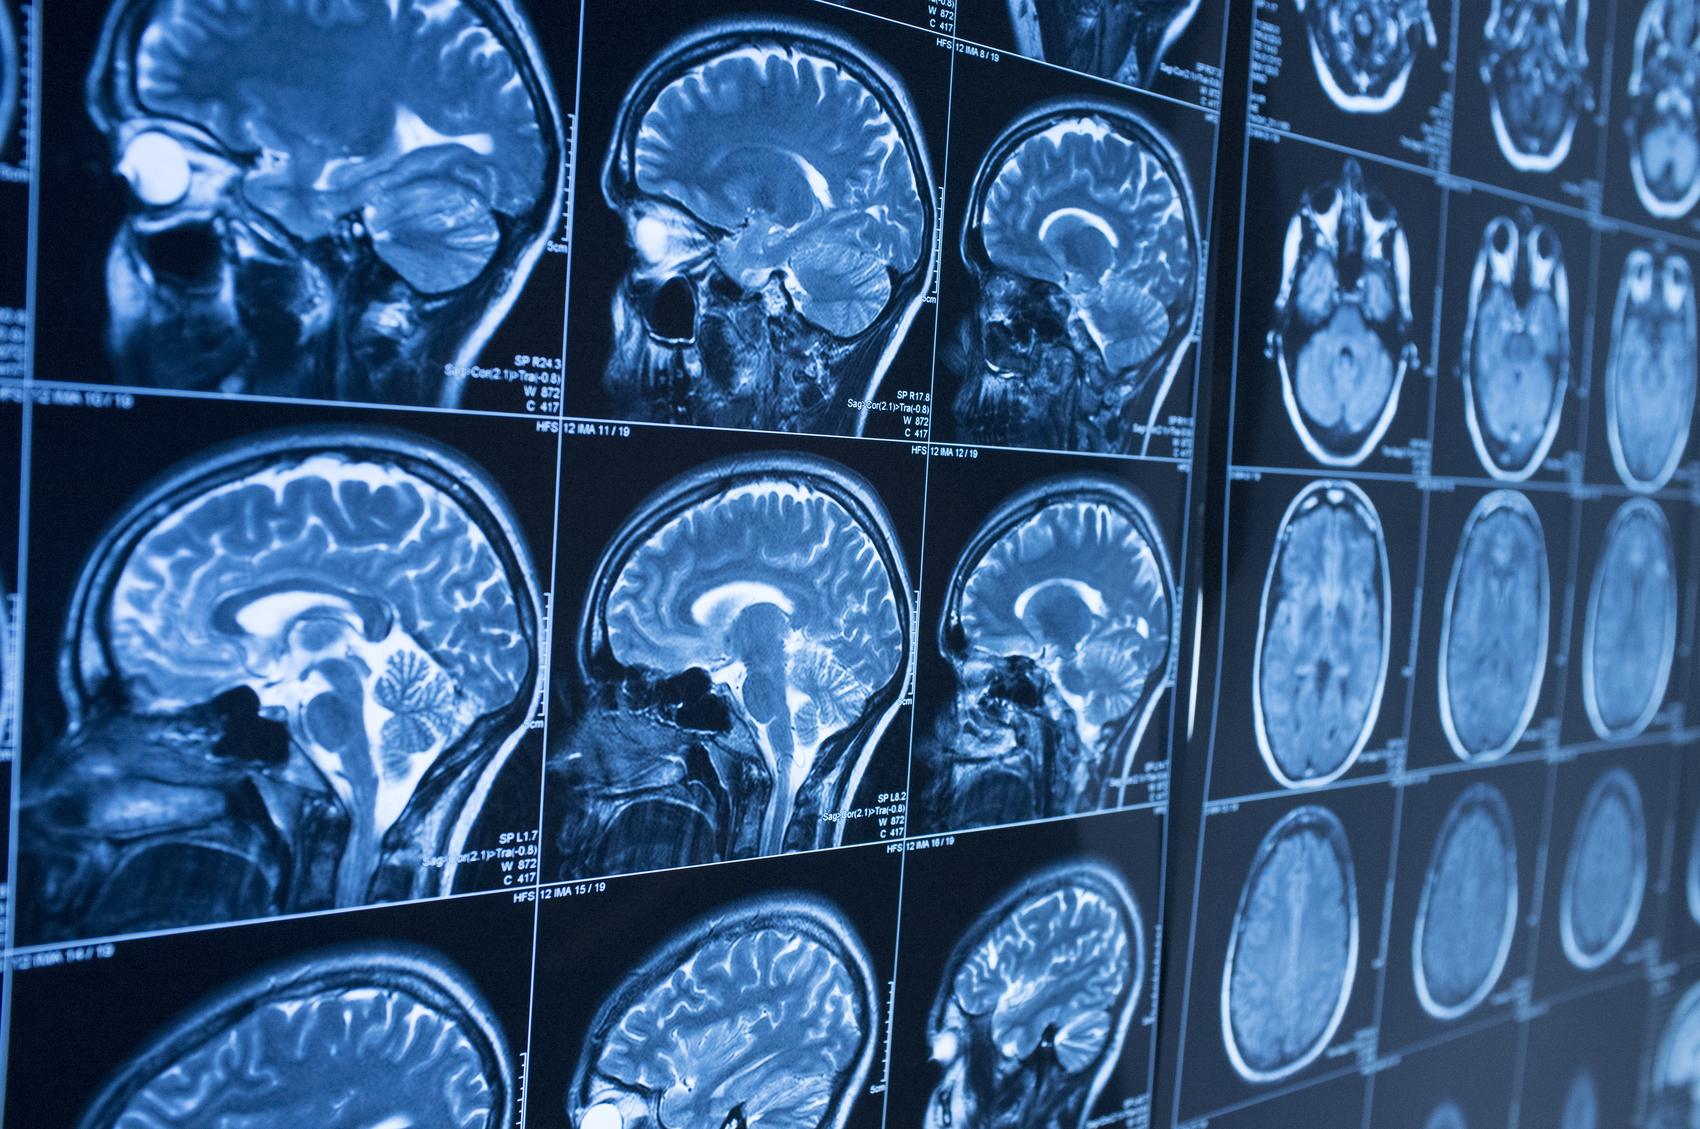

Hemiplegia is a medical condition that causes paralysis on one side of the body. It occurs when damage to the brain affects the areas that control movement and can seriously limit a person’s ability to move and care for themselves.

Hemiplegia usually results from a brain injury or stroke and can cause people to lose all movement on one side, but some keep partial function. In many cases, symptoms appear suddenly after a stroke or injury cuts off blood flow to the brain.

Several health problems can lead to hemiplegia. Stroke is the most common, followed by brain injuries from accidents or falls. Cerebral palsy, brain tumors, and infections can also cause one-sided paralysis.